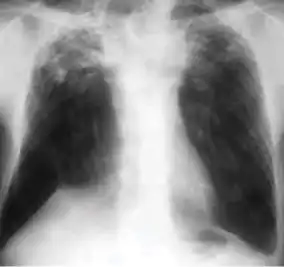

5. Other—Any other finding suggestive of prior TB, such as upper lobe bronchiectasis. Bronchiectasis is bronchial dilation with bronchial wall thickening.

Chest x-ray showing course bronchiectasis of the lungs post-primary pulmonary tuberculosis.